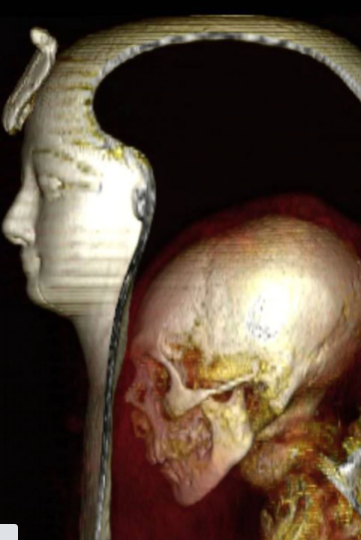

Durante décadas, los investigadores se negaron a descubrir el cuerpo momificado del faraón egipcio Amenhotep I. Y no por miedo a una maldición milenaria, sino porque su envoltorio se presentaba perfectamente conservado y bellamente decorado, con su máscara facial realista incrustada con piedras de colores.

Pero ahora el faraón ha sido visto desnudo por primera vez, después de tres mil años de haber sido momificado, gracias a la nueva tecnología de escaneo de topografía computarizada (TC) y sin que nadie le quite una sola de las vendas que lo cubren.

La “desenvoltura” digital de la momia, decorada con guirnaldas florales, se realizó utilizando escáneres de alta tecnología. Así, los egiptólogos pudieron encontrar detalles desconocidos sobre su apariencia, además de las lujosas joyas con las que fue enterrado, según publicó la BBC.

“Al desenvolver digitalmente la momia y ‘despegar’ sus capas virtuales (la mascarilla, los vendajes y la propia momia) podríamos estudiar a este faraón bien conservado con un detalle sin precedentes”, añadió.